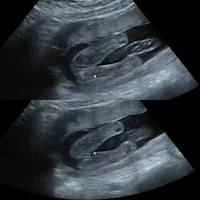

性別 女の子 赤ちゃん エコー- 妊娠14週の性別判断について。 待望の第二子、妊娠中です。 写真は、先日13週目の検診でいただいたエコー動画の一部です。 これはもしや男の子かな?と思えるようなちょこんと出てなんて漠然と思っていたので、19週頃に言われた性別から変わった方がいたり、周りにいたという方の話をお聞かせいただきたく^_^ こないだの検診19w3dの時に 性別が男の子だと言われました🐘

男の子の性別判定はいつから可能? 男の子の性別判定はいつから可能なのでしょうか? 男の子の性別判定は比較的早く、早くて15週・16週ごろからシンボルが見えてくる ようです! 私 多分これは男の子だね~ と先生に言われ、性別が判明したものの確定とはならず。, 妊娠19週6日の検診で、予想通り男の子と確定しました!, !, !, 妊娠初期 (11週、12週、13週)ベ